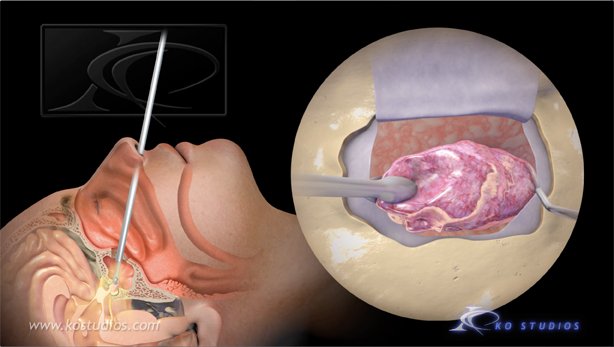

Endoscopic Pituitary Surgery-Nasal Approach

“A pituitary tumor is an abnormal growth of cells within or around the pituitary gland. Most pituitary tumors are non-cancerous growths called adenomas, which do not spread to other parts of the body. However, pituitary adenomas can cause the pituitary gland to produce too many or too few hormones, causing a variety of symptoms.”

This animations depicts tumor removal via the nasal approach.

Copyright©2021: BNI, Authors: KO Studios,

Narration: Dr. Andrew Little

https://www.barrowneuro.org/condition/pituitary-tumors/